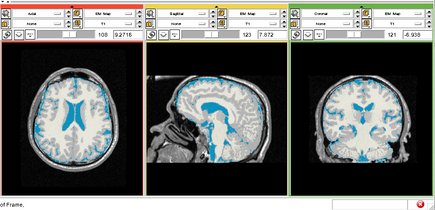

Pediatric MS Study

- Collaborator: Alexander Zaitsev (Brigham and Women's Hospital), MGH and BWH MS Center

- Short description: Evaluate brain atrophy for pediatric MS Patients

- Image specification: 3 Tesla, Scanner: SIGNA HDx / GE MEDICAL SYSTEMS, 3D MPRAGE, Sagital Scans, TR/TI/TE=24/0/7 ms, pixel_xsize = 0.976600, pixel_ysize = 0.976600, fov = 250.009598, aspect = 1.535941, thick = 1.500000, space = 0.000000

- Used Task: MRI Human Brain